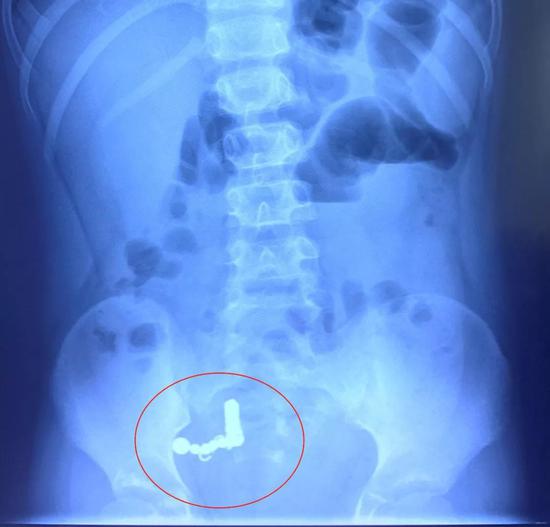

腸道8處穿孔 內(nèi)藏18枚異物

經(jīng)過(guò)一系列檢查

醫(yī)生發(fā)現(xiàn)小博的腸道內(nèi)有十多枚異物

7月16日凌晨1點(diǎn)50分

孩子被推入手術(shù)室

醫(yī)生為孩子實(shí)施消化道異物急診手術(shù)

手術(shù)中

醫(yī)生竟然在小博體內(nèi)發(fā)現(xiàn)磁性方塊4塊、

磁性圓珠7枚、鐵絲圈7個(gè),

腸管穿孔達(dá)8處之多!